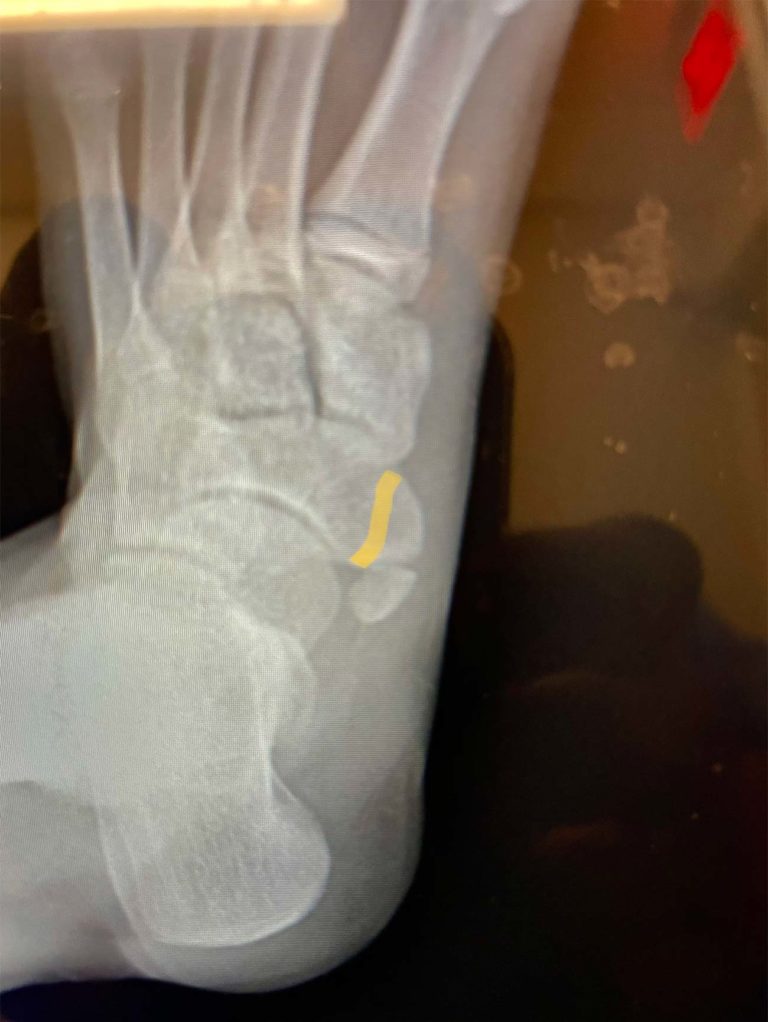

Abstract. Accessory ossicles of the foot are commonly mistaken for fractures. The accessory navicular is one of the most common accessory ossicles of the foot. There is a higher incidence in women and the finding might be bilateral in 50-90%. This entity is usually asymptomatic, although populations with medial foot pain have a higher prevalence.. Classification. The Geist classification divides the accessory navicular bones into three types. Type 1: An os tibiale externum is a 2-3 mm sesamoid bone in the distal posterior tibialis tendon.Usually asymptomatic. Type 2: Triangular or heart-shaped ossicle measuring up to 12 mm, which represents a secondary ossification center connected to the navicular tuberosity by a 1-2 mm layer of.

The accessory navicular bone is one of several accessory ossicles of the foot and is considered as a normal anatomic and radiographic variant (1-10).Accessory navicular bones are classified into three types based on their shape and location in relation to the navicular bone (3-6).Type I is a 2-3 mm sized sesamoid bone in the posterior tibial tendon (PTT) and is referred to as "os tibiale.. The Geist1 classification divides accessory navicular bones into three types: type 1 accessory navicular bone. also known as os tibiale externum. 2-3 mm sesamoid bone embedded within the distal portion of the posterior tibial tendon. no cartilaginous connection to the naviculam tuberosity and may be separated from it by up to 5 mm.